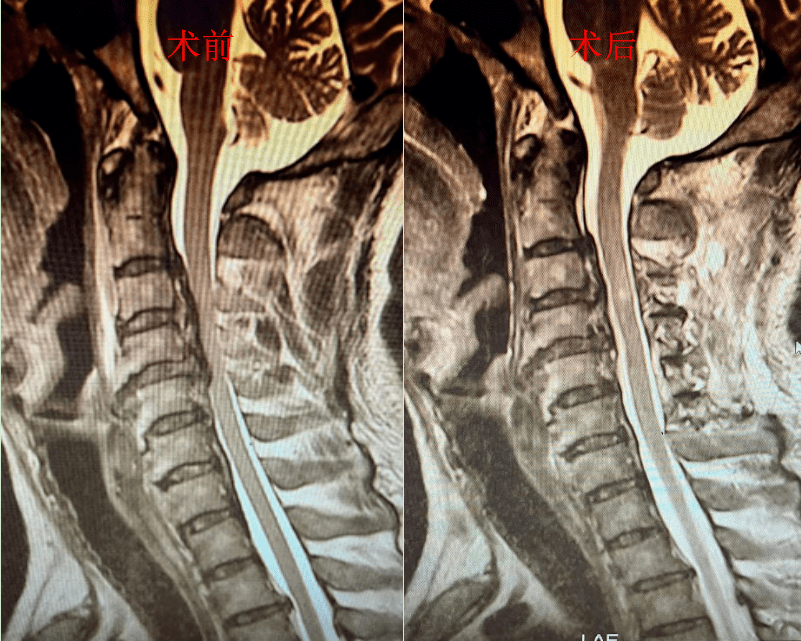

45岁男子摔瘫了,原因竟然是韧带变"骨头"_董先生_颈椎_脊髓